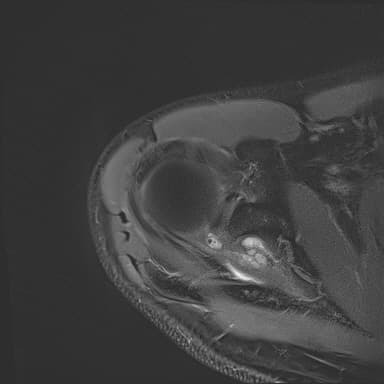

어깨 mri 좀 봐주세요 물혹있다고 하는데 수술해야 하나요?

하도 안 나아서 우측 견관절도 mri 촬영을 했는데 물혹이 있네요

• 1번 째 사진